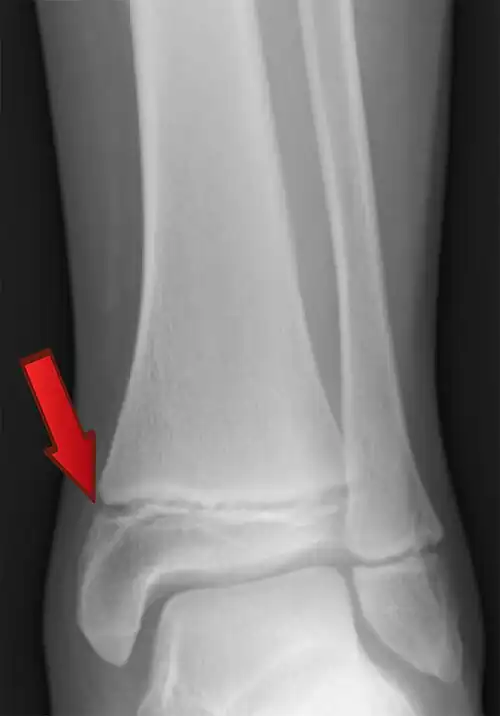

Fisis, también llamado cartílago de crecimiento, cartílago metafisario, placa de crecimiento o placa epifisaria, es una zona de los huesos largos de niños y adolescentes, que se encuentra ubicada en la metáfisis.

Esta placa de cartílago, permite el crecimiento del hueso en edades de desarrollo. Su espesor y función es máxima en la infancia. Cuando se llega a la pubertad la fisis empieza a decrecer y desaparece por completo, alrededor de los 25 años.

Los trastornos en esta placa, tiene consecuencias negativas en el crecimiento del hueso.

Los cartílagos de crecimiento son más débiles que el hueso sólido. Esto hace que sea más probable que sufran lesiones.[11]

Las alteraciones y enfermedades del cartílago de crecimiento o fisis,[10] incluyen:

- Fracturas. Como Epífisis capital femoral deslizada.